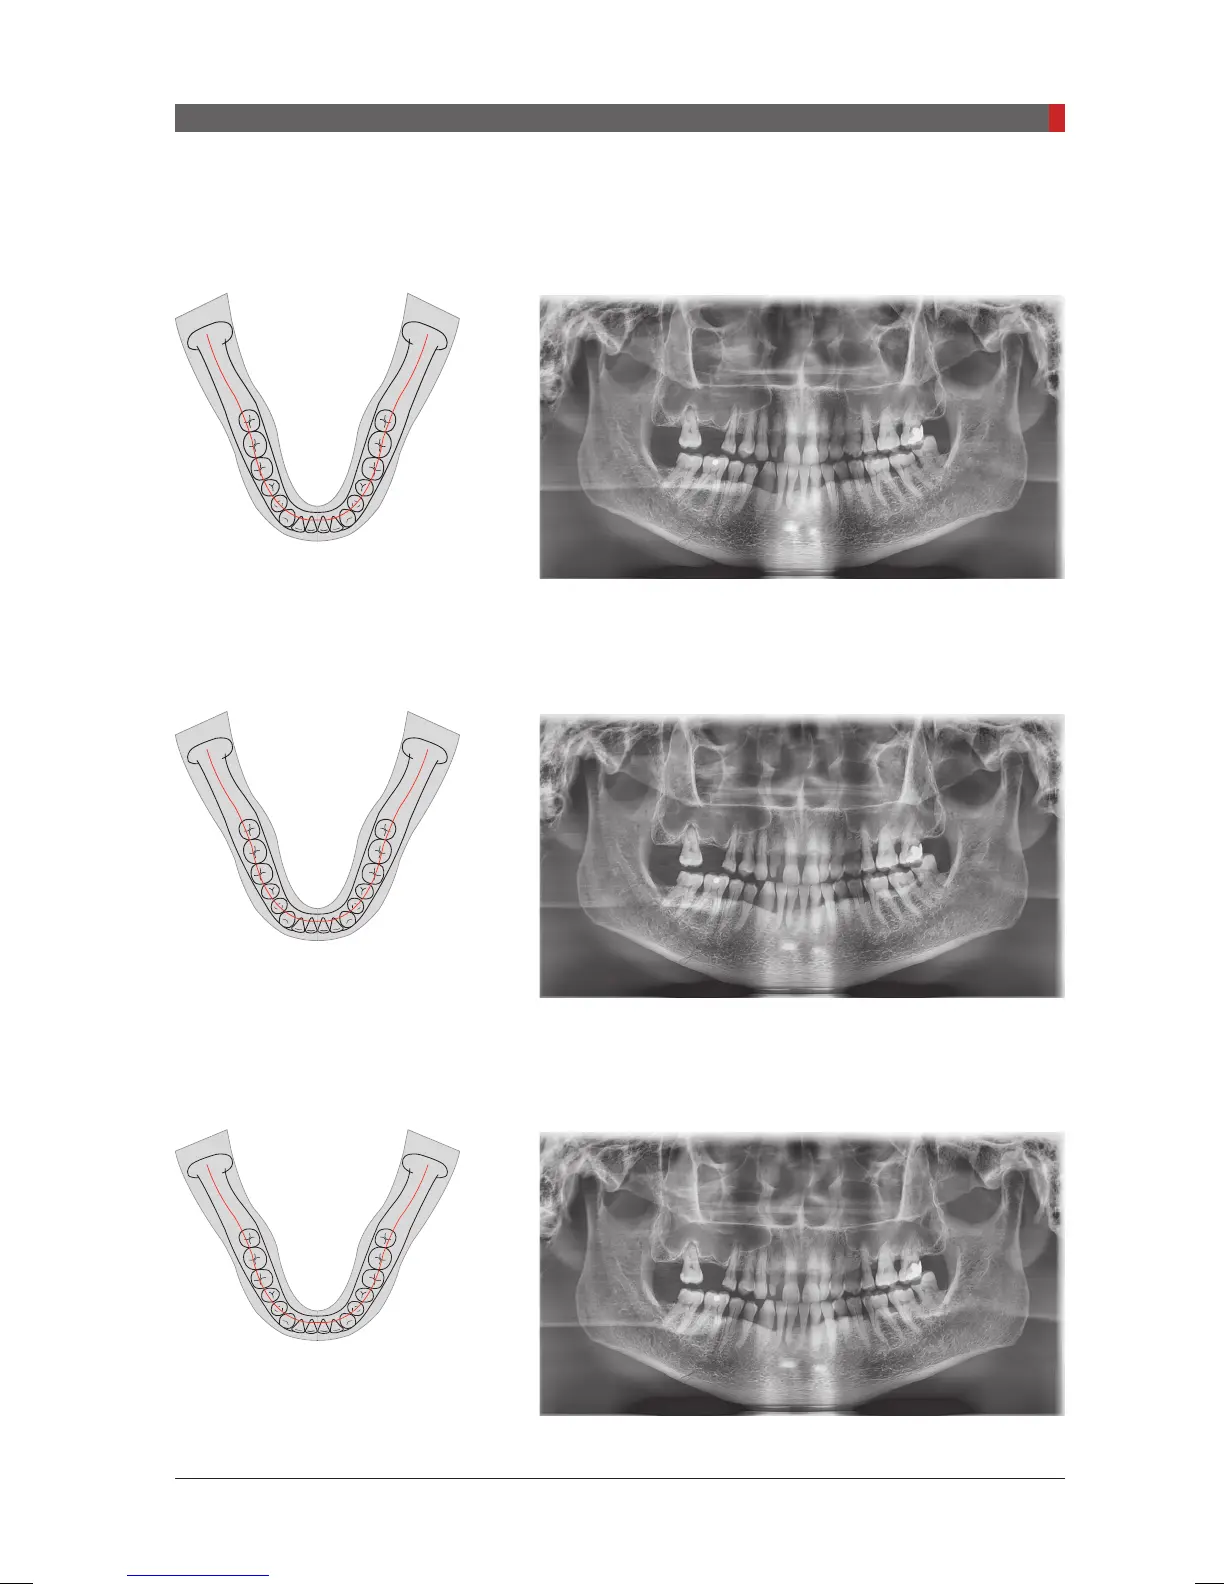

Narrow_Standard

A panoramic imaging mode for the patients with the V-shaped

arch trajectory (typically for some females).

Normal_Standard

A panoramic imaging mode for the adult patients with the

normal arch trajectories.

Wide_Standard

A panoramic imaging mode for the patients with the square-

shaped arch trajectory (typically for some males).